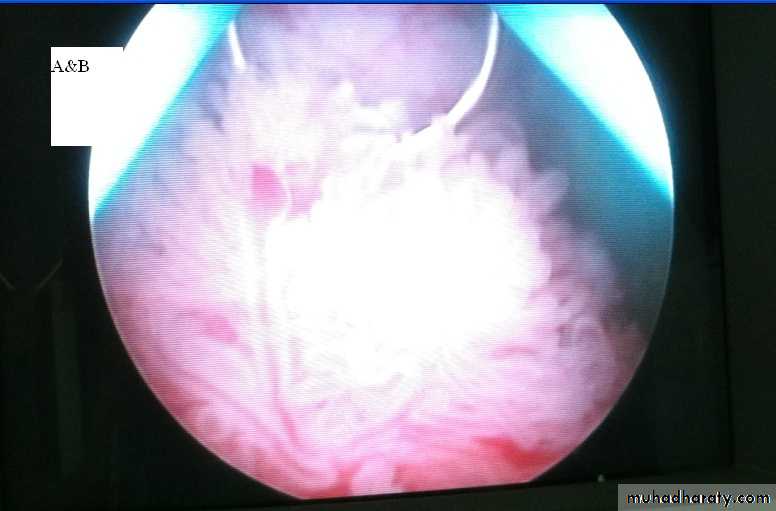

History of Hematuriabladder tumor (stageTa-T1)